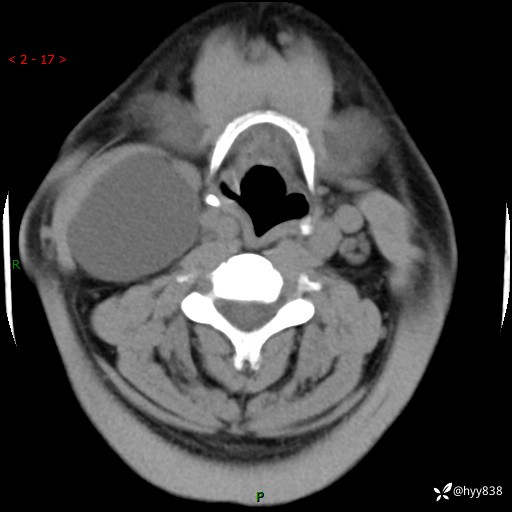

颈部CT平扫+增强